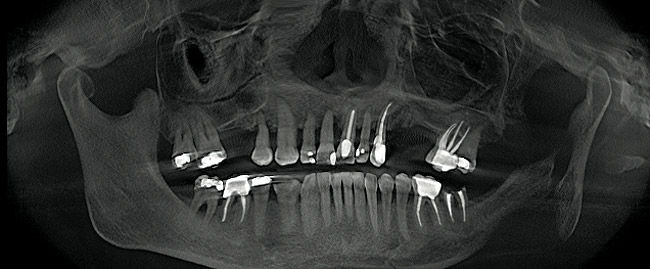

Figure 13  Pretreatment panorex demonstrating hopeless condition of maxillary dentition as well as mandibular molar teeth.

Figure 13